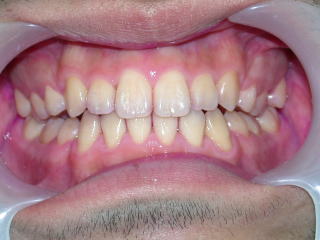

平成24年6月9日、だいぶ閉じてきました。

装置除去平成25年5月1日

完全に閉じました。